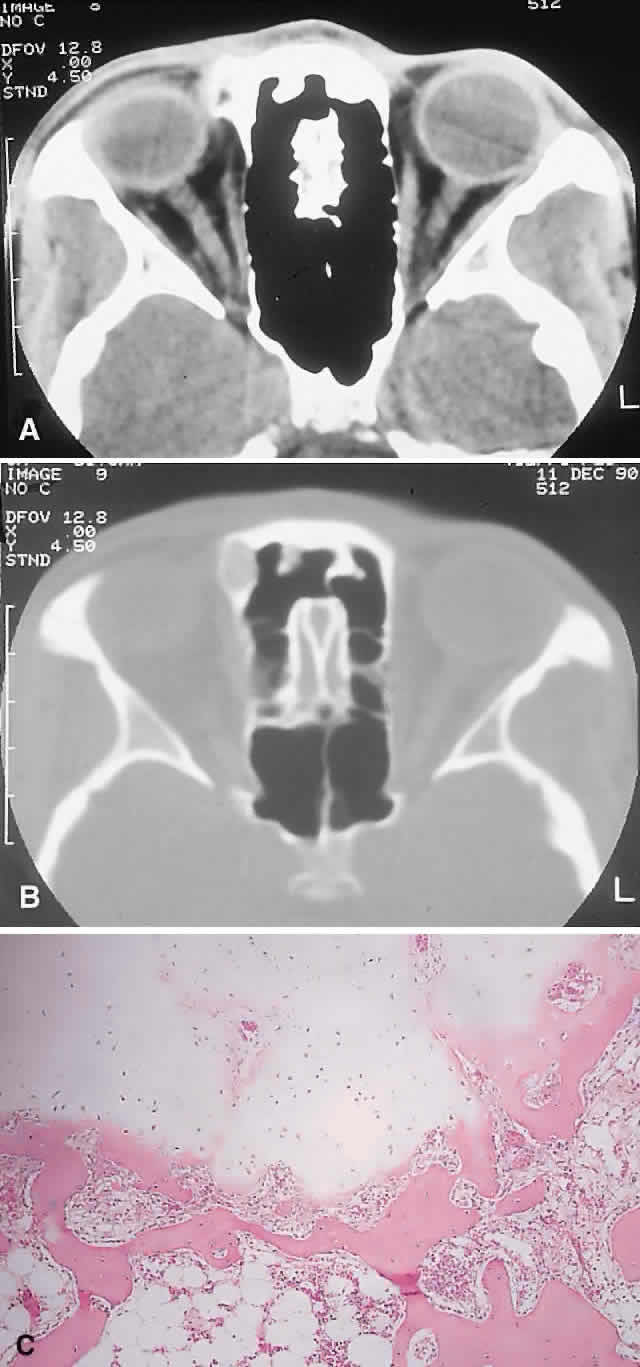

| The above clinical patterns correlate reasonably well with the following